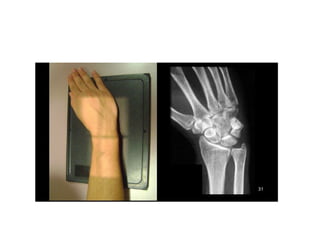

INCIDÊNCIAS PUNHO E MÃO

• #13 ADUÇÃO/ABDUÇÃO – DESVIO ULNAR/RADIAL – FLEXÃO/EXTENSÃO – INVERSÃO/EVERSÃOP